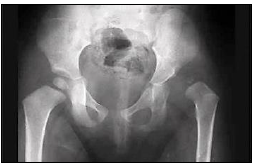

Considere uma criança com sinal de Trendelemburg positivo e a seguinte radiografia com quadril:

É correto afirmar que trata-se de